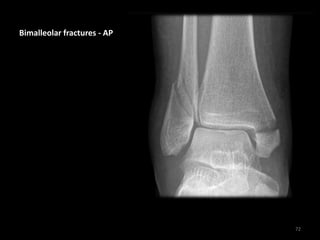

Bimalleolar fractures - AP

72

• Transverse medial

malleolus fracture

• Lateral malleolus

fracture - at level

of ankle joint (WeberB)

• Joint widened medially

due to lateral

displacement of the

talus